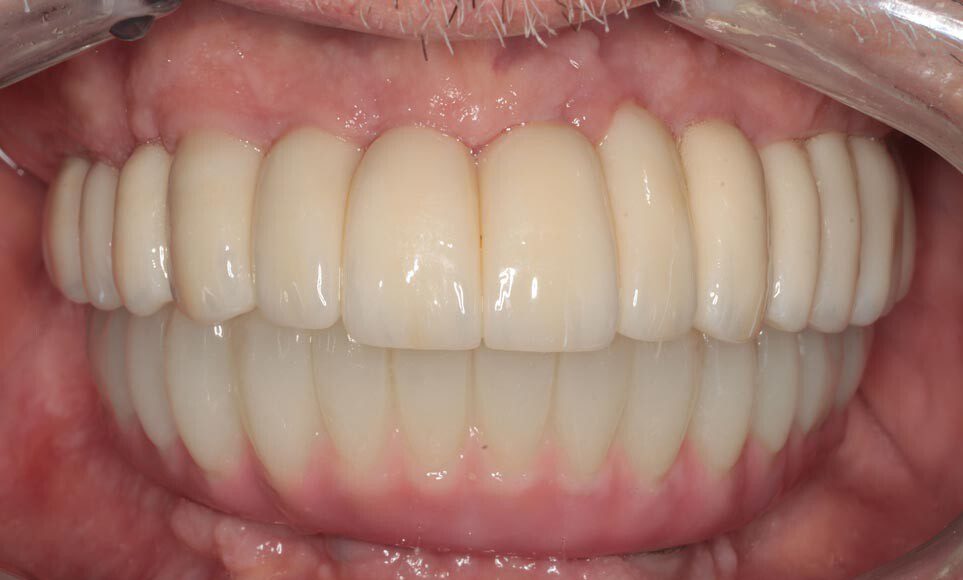

Frontal temporary smile. The patient heals for two additional months and returns to start the process for fabrication of the permanent implant bridges. We begin by assessing and photographing the temporary bridges. There are several issues with the first temporary bridges. Mainly, because he wore his original denture after the first surgery, we were unable to correct the left-to-right cant (slant) until now.